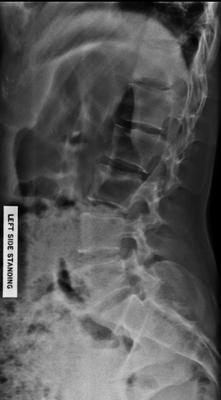

Your lumbar spine has an anomaly called a lumbarisation - six vertebrae instead of five. What is good is that the L6 appears well nested, but there are accessory joints visible, all likely to cause pain periodically.

And thirdly there's a suggestion of a short leg giving you a significant curvature; that's where I would suggest you start, though how much and whether it should be a full inner or just under the heel is a decision that needs to be made.